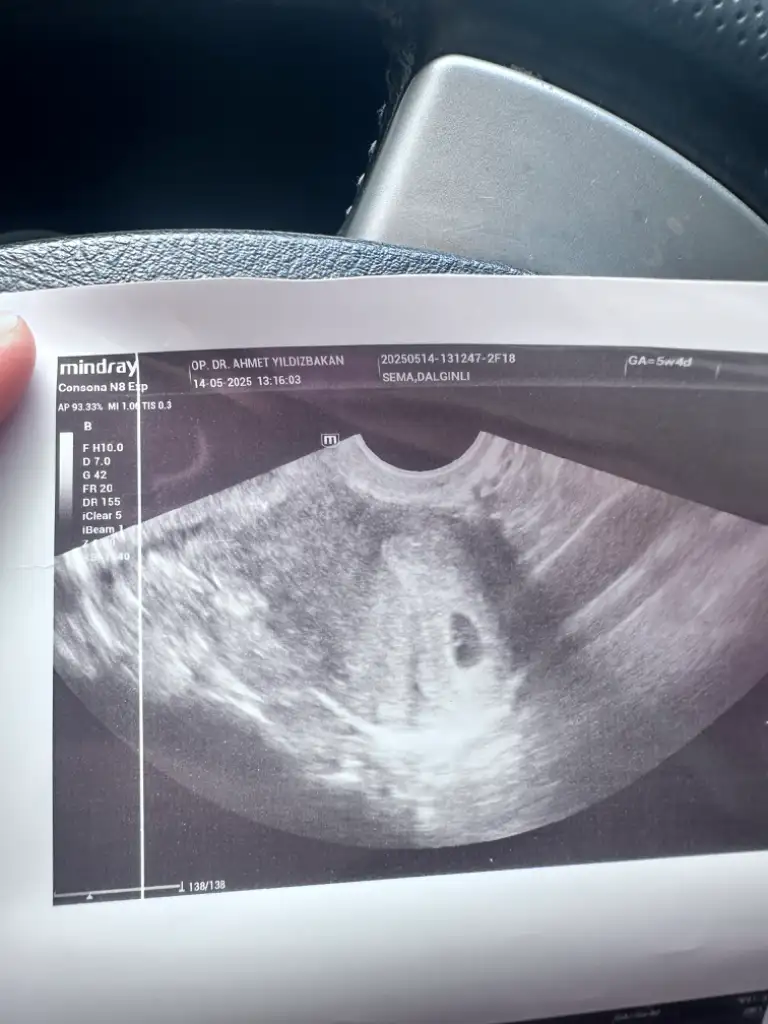

Benimkinede alttan baktı ama kaç haftalık olduğu yazmıyor ultrasyon kâğıdında ama seninkinde bebiş gözüküyor tektas gibi duruyor hayırlısı olsun bakalım 😇

5+4 haftalıksın cnm ultrasyon kâğıdın öyle dior

Sağol canım kesenin görüntüsü normal mi doktor dedi bebek oluşmuş 10 gün sonra kalp atışı için çağırdı